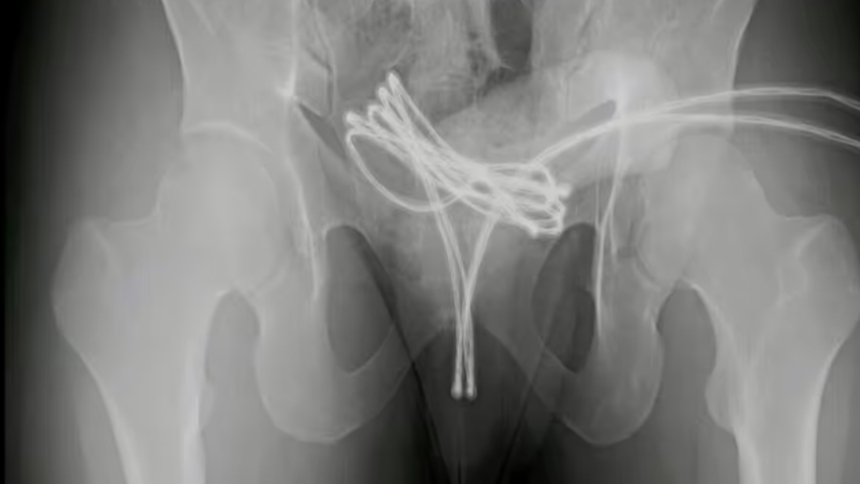

Al ver que no podía retirarlo, el joven decidió acudir a un hospital cercano. Los médicos determinaron que el cable se alojó profundamente en su vejiga y, gracias a las radiografías, descubrieron que estaba doblado dentro de su cuerpo.

Los médicos intentaron retirar el cable con métodos manuales y no invasivos, pero podrían causarle severos daños. En ese sentido, optaron por llevarlo al quirófano, darle anestesia general y retirarlo mediante una cirugía en la Facultad de Medicina de la Universidad Drexel de Pensilvania.